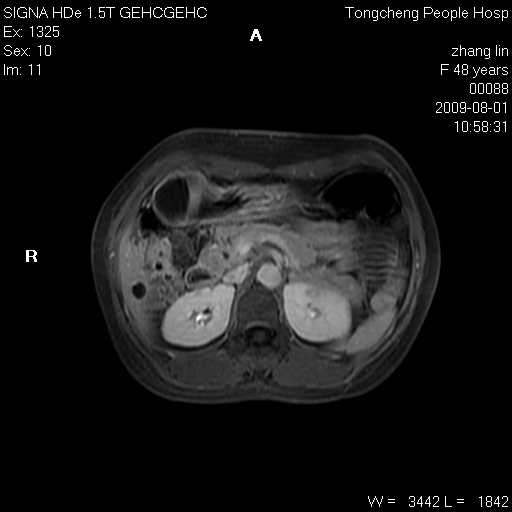

女,48岁。健康体检,彩超发现右肾占位性病变。平素健康。

临床诊断:右肾占位性病变,性质待定(囊肿?肿瘤?)。

上中腹部mr平扫+增强扫描,图像如下:

右肾上极见一类圆形病灶,t1wi呈等信号t2wi呈等高混杂信号,三期增强无强化,边界清---考虑囊肿出血。

同反相位均表现为等信号,病变无强化,考虑含蛋白的囊肿可能,弥散加权相或许有些帮助,